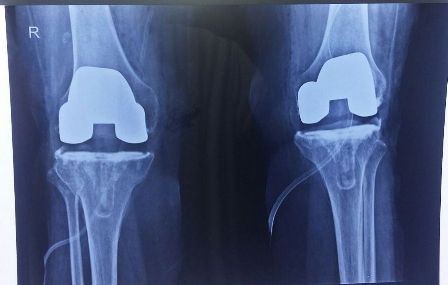

Patient : Mrs. Urmil Devi

Age / Sex : 63 yrs Female

Procedure : TKR Right Side Done

• A case of Rheumatoid Arthritis from last 20 years.

• Fixed Flexion Deformity both knee joints 90 degrees.

• Same sitting both knee Arthroplasty done.